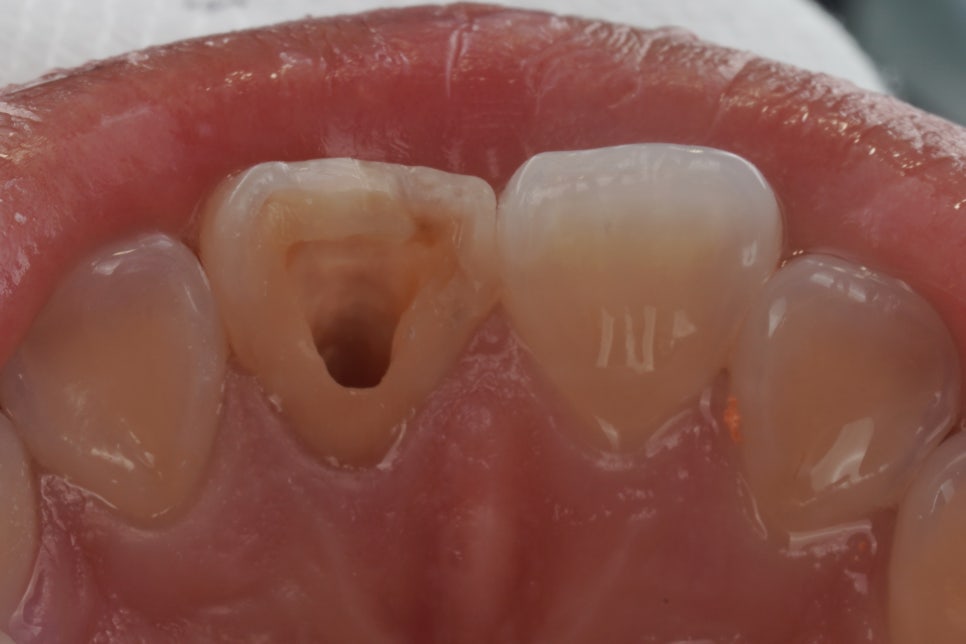

먼저 신경치료가 되어 있는 치아를 열어서 안쪽 상태를 확인하는 과정을 거쳐요.

그리고 변색의 원인이 될 수 있는 신경관 입구 쪽의 약재나 충전물을 정리해 줍니다.

그다음에는 치아 내부 공간에 미백 약제를 넣어서 일정 시간 작용하도록 하는데요. 이 약제에서 산소가 발생하며 조금씩 밝게 만들어 주는 원리에요^^

치아 상태에 따라 한 번으로 끝나는 경우도 있지만 보통은 몇 차례 반복하면서 주변 인접치와 자연스럽게 어울리는 색을 맞춰 가고 있어요.

완료 후

한 2주 정도 기다리면 이렇게 건강한 자연치와 같은 모습으로 바뀌게 된답니다^^

그래서 특히 젊은 환자분들의 경우에는 실활치 미백 → 레진 홀 메우기 이렇게만 하셔도 크라운 없이 하얀 치아를 얻을 수 있습니다.

크라운 없이 치료 완료

저는 치아는 한 번 삭제하면 다시 되돌릴 수 없기 때문에 살릴 수 있을 때 살려야 한다는 생각으로 매 진료에 임하고 있어요.